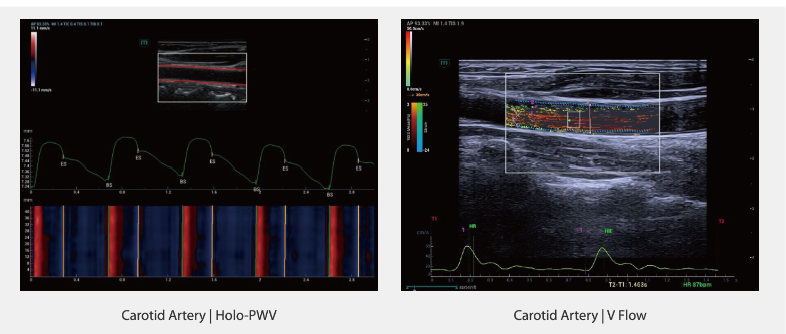

Quantitative Vascular Analysis Tools

Система Resona A20 представляет новое поколение инструментов для количественного анализа сосудов, основанных на RF-данных (радиочастотных данных). Эти технологии включают измерение скорости распространения пульсовой волны в сосудах (PWV) и анализ напряжения сдвига стенки сосуда (wall shear stress). Данные улучшения помогают в оценке состояния артерий.

Holo-PWV — измерение скорости распространения пульсовой волны для оценки эластичности сосудов

V Flow и анализ напряжения сдвига стенки (V Flow and wall shear stress analysis) — визуализация кровотока и его воздействия на стенки сосудов

Сонная артерия | Holo-PWV**

Сонная артерия | V Flow**